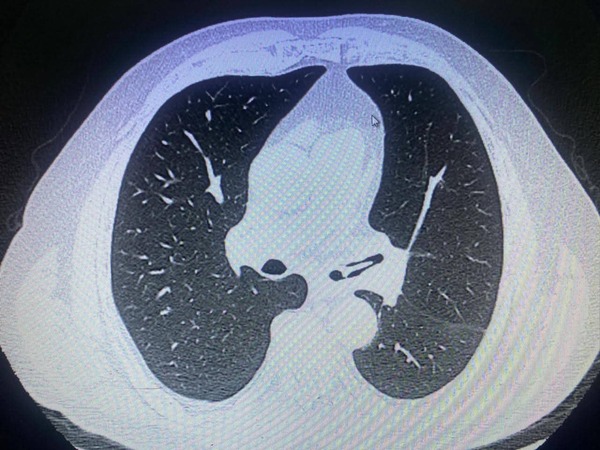

Popular / Karai ijahy’o pa’ ã con hueso de pollo y tuvo que ser operado

El Doctor Carlos Morínigo, del INERAM, relató los malos momentos que ohasa un karai de 68, oriundo de Carapeguá, upéi de que en un almuerzo había sido ijahy’o pa’ã con un huesito de pollo, que no fue detectado a tiempo, por lo que tuvo que ser intervenido quirúrgico.  “Para ir cerrando el año… solo en […] ...[Leer más]